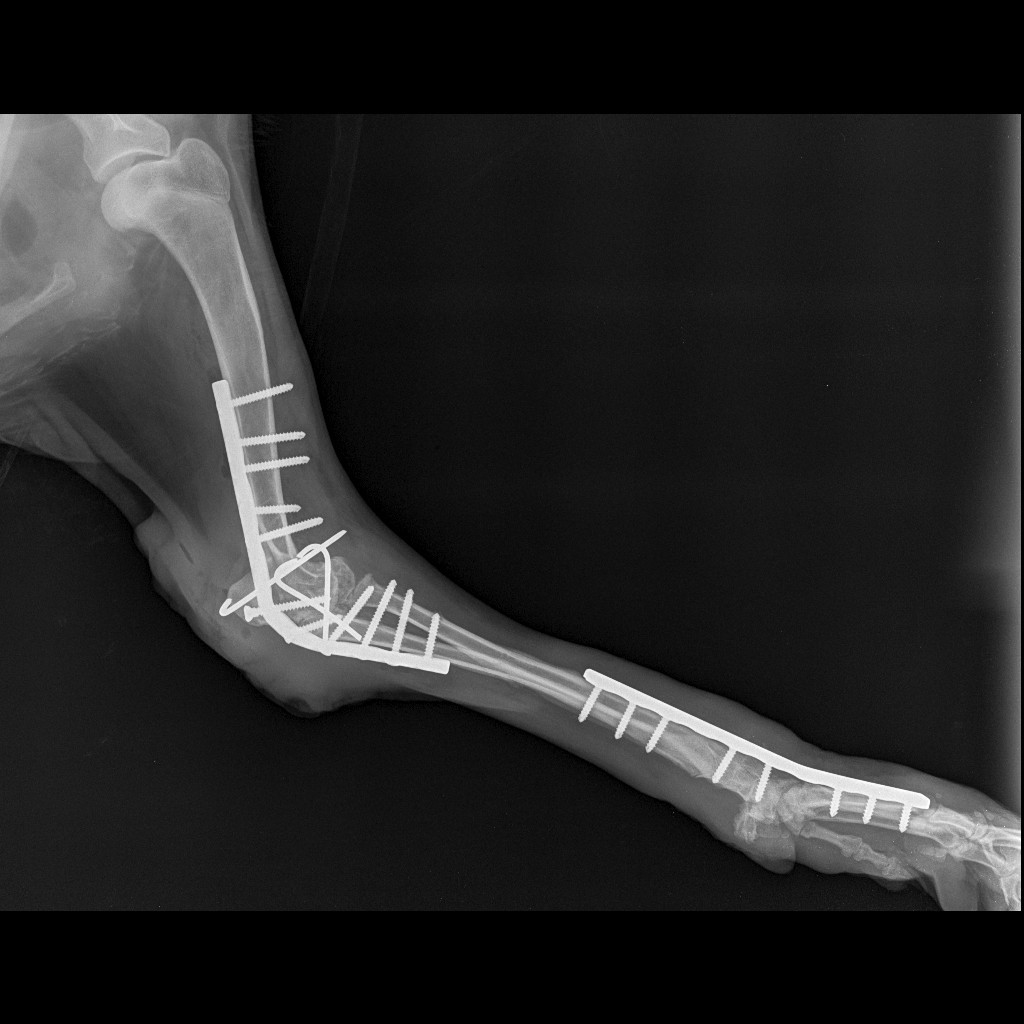

После операции и продолжительного лечения, задняя лапка полностью восстановилась, а вот передняя, после артопротезирования, которое сделали в городе Лида в клинике «Кот Бегемот», требует реабилитации.